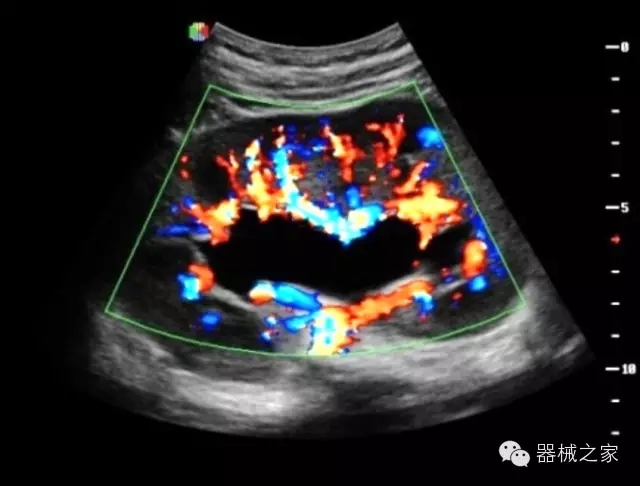

臨床圖片賞析

·智能微血流成像技術(shù):智能微血流捕捉技術(shù)可以提取出隱藏在背景噪聲中的弱血流信號(hào),大大提高低速血流的敏感性;

·高效3D/4D成像技術(shù):高速的4D幀頻,豐富的3D成像模式,智能斷層切片功能;